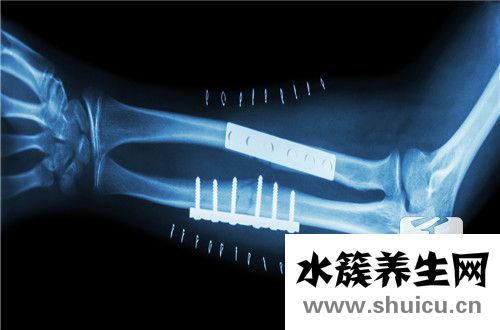

橫切面位于椎間盤位置。如果產生橫突骨折的話,不良影響會非常大。如果不重視,往往會造成嚴重的狀況。一般來說,這種骨折需要兩個月才能修復,患者需要臥床休息,以防骨折很快。如果要鍛煉身體,最好戴上椎...